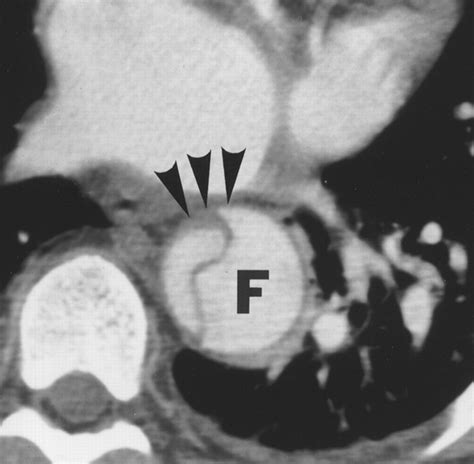

The primary goal of the Aortic Dissection CT is to identify the "intimal flap"—the physical separation of the aortic layers. Radiologists categorize these findings based on the Stanford or DeBakey systems, which help surgeons decide the urgency of the repair. The report will typically detail several critical features:

Intimal Flap The presence of a visible tear separating the true and false lumens.

False Lumen The space formed between the aortic layers that fills with blood.